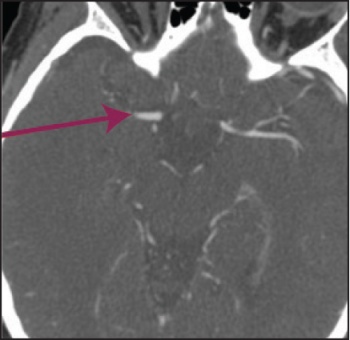

See Figures 1(i)-3(ii) for images of a successful endovascular therapy case.

Figure 1 (i): this and Figure 1(ii) show axial and coronal CT angiogram identifying proximal right MCA (M1) occlusion(click to enlarge)